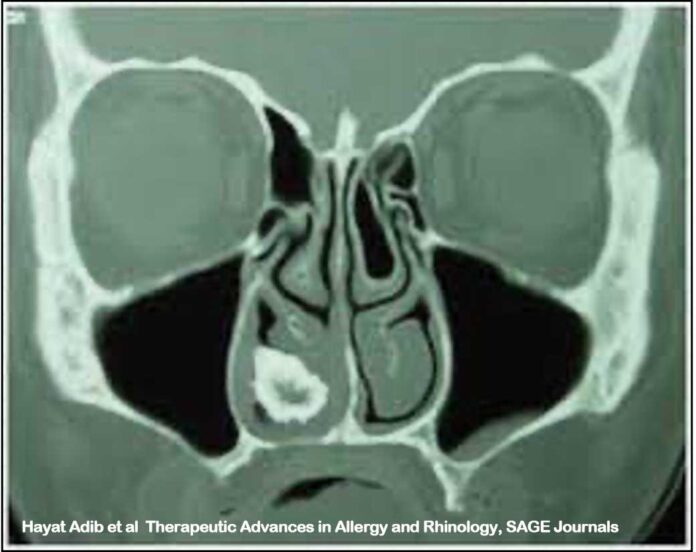

La TAC dei seni paranasali va sempre fatta per avere una definizione spaziale dettagliata e riscontrare eventuali complicanze. Il rinolita si presenta come una opacità ad alta densità, contorni irregolari, con un’area ipodensa al centro.

La TC talvolta aiuta a riconoscere l’origine esogena (corpo estraneo) o endogena ed a discriminare con la diagnosi differenziale con osteoma, polipi calcifici, sequestri ossei (sifilide, radioterapia), osteosarcoma and chondrosarcoma.